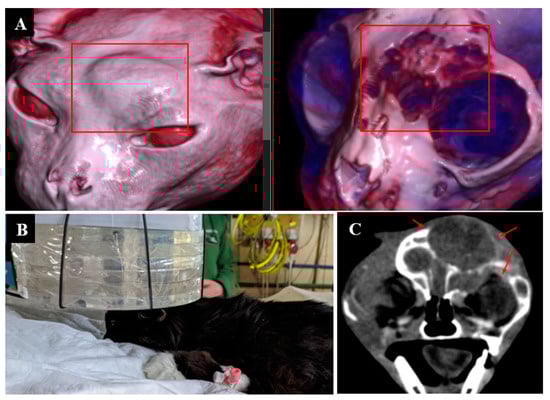

3.8. Case 8

3.9. Case 9

4. Discussion